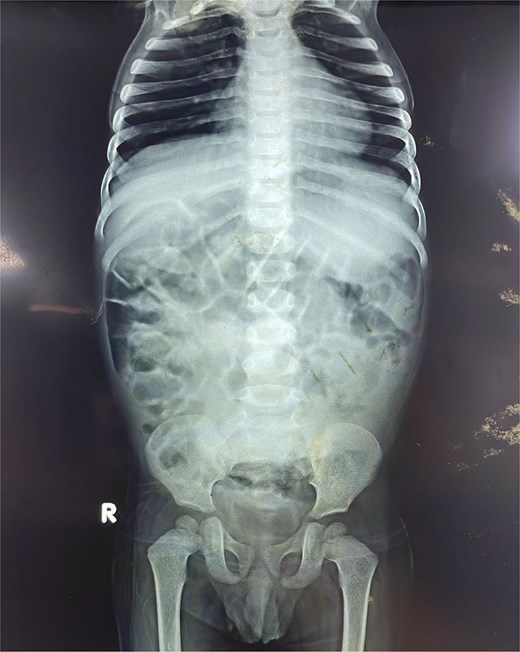

Initial plain radiographs of the abdomen and chest (Fig. 1) revealed diffusely air-distended bowel loops but no air-fluid levels or pneumoperitoneum, suggesting a partial obstructive process. An abdominal ultrasound performed during a prior admission had identified a 6.0 × 5.0 cm thick-walled, fluid-filled gut segment in the right iliac fossa, provisionally diagnosed as a Meckel’s diverticulum.

Anteroposterior abdominal radiograph demonstrating diffusely air-distended small bowel loops consistent with a partial small bowel obstruction. No significant air-fluid levels or evidence of pneumoperitoneum is visible.